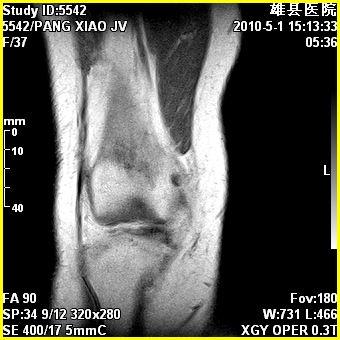

标题: MRI2894:患者右膝关节疼痛两月余,无明显外伤史 [打印本页]

标题: MRI2894:患者右膝关节疼痛两月余,无明显外伤史

右股骨下端前内侧类圆形异常信号,位于干骺端,呈长t1长t2改变,但信号不均,t1图上病灶中心见小片状稍高信号影,t2图上见散在稍低信号影,stir像呈高信号,因病灶较小,缺乏特征性改变,结合患者年龄及部位,考虑嗜酸性肉芽肿可能性大。胫骨关节面下的小囊状异常信号,如果一元论考虑则为嗜酸性肉芽肿,不过发生在这个部位的少见,二元论考虑为邻关节骨囊肿。半月板与前后交叉韧带均未见异常。

右股骨下端前内侧干骺端囊性良性病变,考虑 1内生软骨瘤 2骨囊肿 3肉芽肿。

年龄略大 内生软骨瘤?

骨样骨瘤?内生软骨瘤?